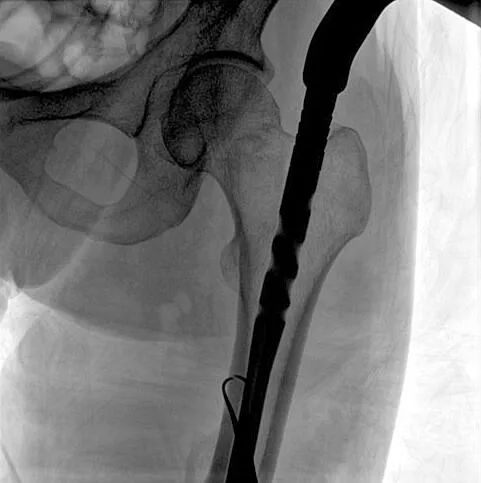

大平板一體式C形臂輔影像

在進(jìn)行髓內(nèi)釘內(nèi)固定術(shù)時(shí),醫(yī)生需要同時(shí)觀察到入釘點(diǎn)和骨折部位的情況,普愛醫(yī)療大平板一體式C形臂采用30CM×30CM的平板探測器,能夠呈現(xiàn)更廣闊的成像面積,滿足大部分長骨髓內(nèi)釘內(nèi)固定術(shù)的攝片需求。

大平板一體式C形臂成像面積

術(shù)中定位準(zhǔn)確、出血量少,術(shù)后影像顯示股骨移位糾正,恢復(fù)良好力線,手術(shù)效果良好。